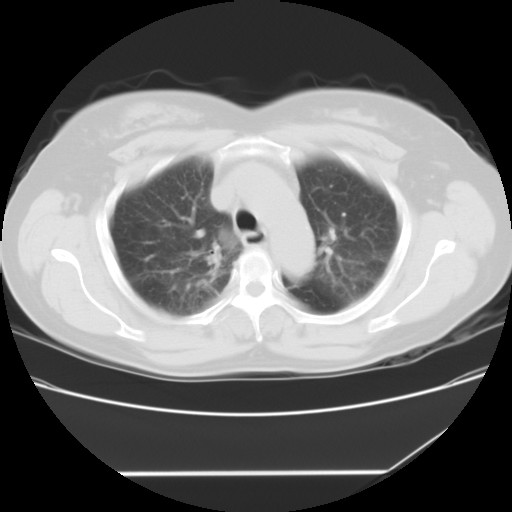

女性,62岁,长期咳嗽,既往从事工作有粉尘接触,有高血压病史,110/150mmhg,近日咳嗽加重,脸面浮肿,请大家帮看下,

间质性肺炎,有纤维化趋势。

1)慢性支气管炎并肺部感染、肺气肿。2)肺间质纤维化。

间质性肺炎,左下肺机化性肺炎。